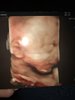

załączam fotkę, niezbyt twarzowa, bo Mały się pępowina bawił <3

Zobacz załącznik 867446